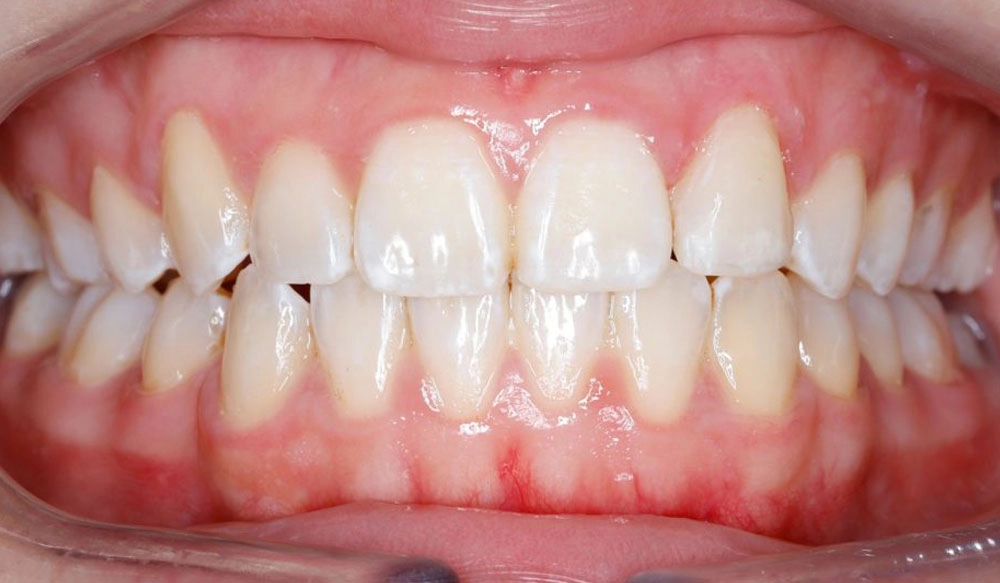

Crowding

Crowding is the condition in which there is a discrepancy between tooth size and space available for the teeth to be aligned in the dental arch

Patient Information:

Age: 17

Gender: female

Invisalign Treatment Option: Invisalign Comprehensive

Total Treatment Time:

29 months